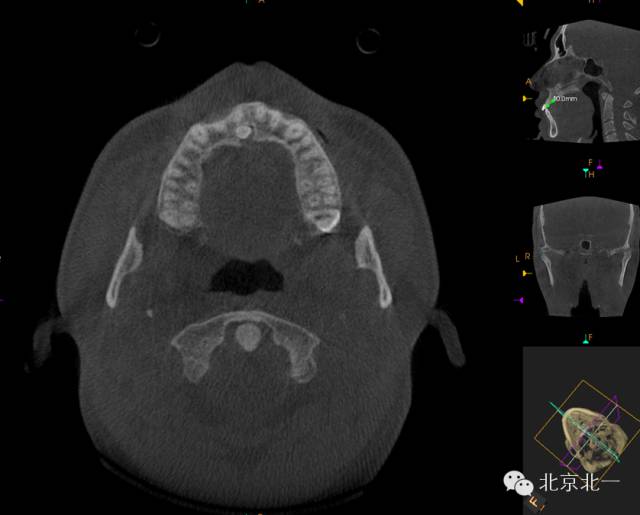

CBCT顯示埋伏多生牙位于腭側(cè)高位,接近切牙管開(kāi)口位置。

CBCT冠狀位顯示多生牙位于鼻腭神經(jīng)管